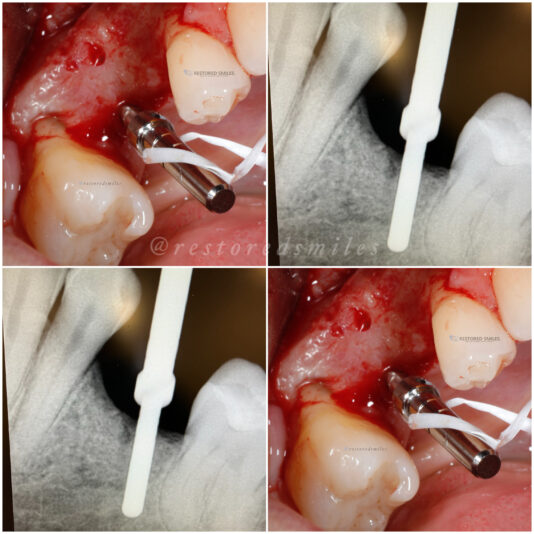

• Looks good, right?!? Not once you see the cbct and create a larger full thickness flap. What would you do here? What are your options? This happened during one of our live surgery courses. Please leave a comment below on what you would do and a couple options we may have. After I recieve several comments I will post a follow up post next week…

Read more

• implant position looks too buccal to me in this photo. i’d remove and start a new osteotomy and sink the implant to the level of the lingual bone